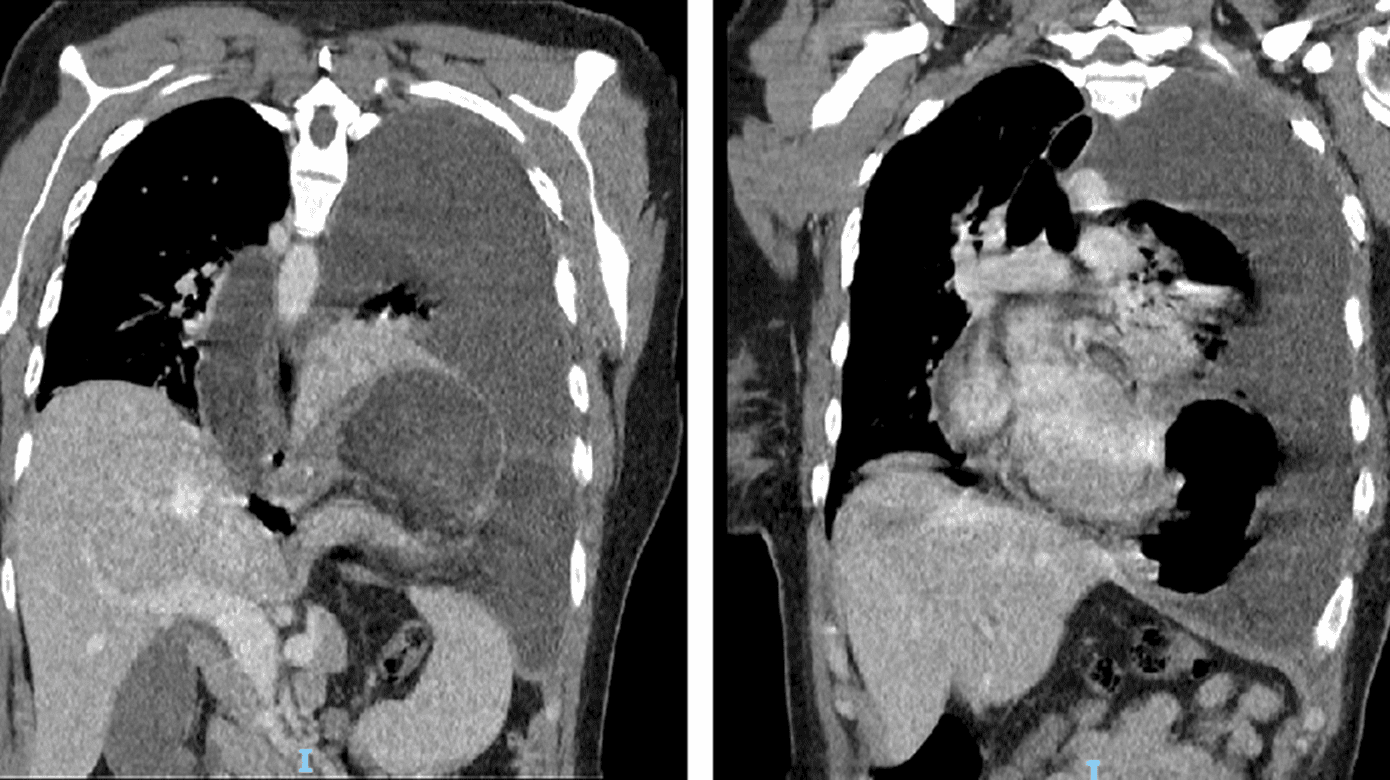

En CT af thorax viste herniering af ventriklen til thorax, inkarceration, stort pleuraekssudat, udbredt atelektase og højreforskydning af mediastinum (Figur 1). Recidivet var hidtil ukendt.